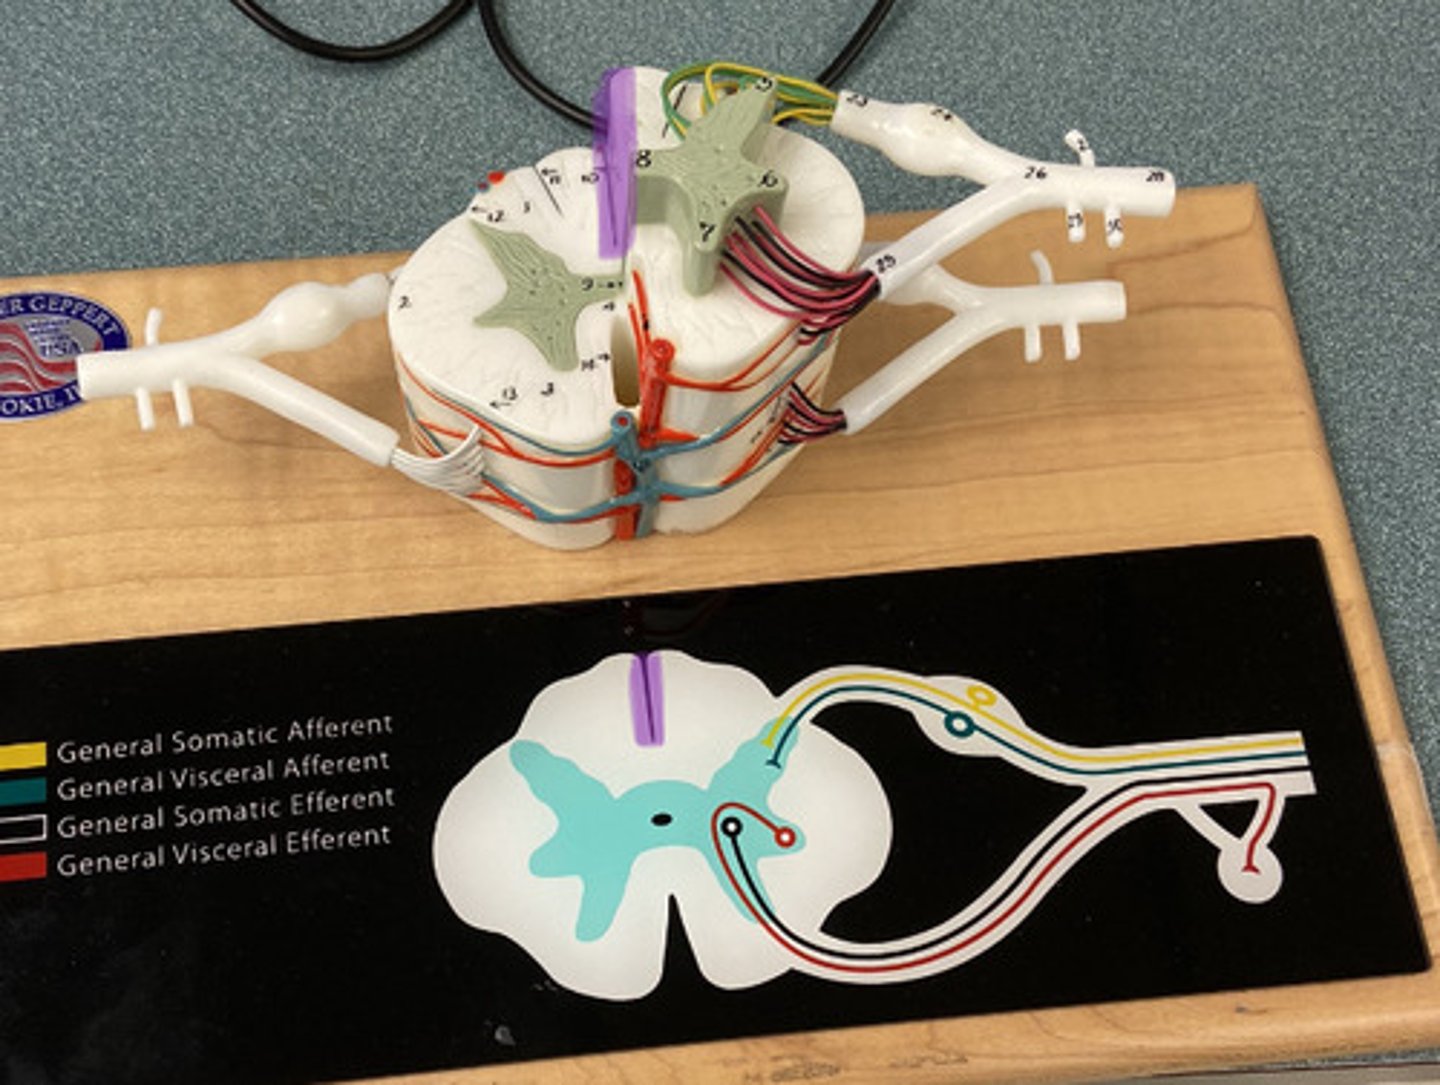

White Columns/ Matter

Gray Matter

Dorsal Horn

Lateral Horn

Dorsal (posterior) Median Sulcus

Ventral (anterior) Median Fissure

Central Canal

Ventral Root

Dorsal Root

Dorsal Root Ganglion